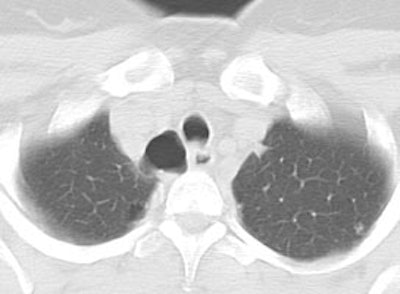

Tracheal diverticulum: The patient shown below was being evaluated for active pulmonary tuberculosis and was incidentally discovered to have a tracheal diverticulum. Note the slightly irregular wall of the diverticulum which can be seen in almost one-third of cases. Click here to view cine image which nicely confirms communication with the trachea. |